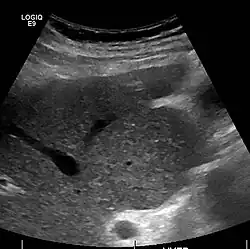

Caudate lobe hypertrophy on ultrasound due to cirrhosis

Imaging

Ultrasound is routinely used in the evaluation of cirrhosis.[45] It may show a small and shrunken liver in advanced disease. On ultrasound, there is increased echogenicity with irregular appearing areas.[64] Other suggestive findings are an enlarged caudate lobe, liver surface nodularity[65] widening of the fissures and enlargement of the spleen.[66] An enlarged spleen, which normally measures less than 11–12 cm (4.3–4.7 in) in adults, may suggest underlying portal hypertension.[67] Ultrasound may also screen for hepatocellular carcinoma and portal hypertension.[45] This is done by assessing flow in the hepatic vein.[68] An increased portal vein pulsatility may be seen. However, this may be a sign of elevated right atrial pressure.[69] Portal vein pulsatility is usually measured by a pulsatility index (PI).[68] A number above a certain value indicates cirrhosis (see table below).

Portable ultrasound is a low-cost tool to identify the sign of liver surface nodularity with good diagnostic accuracy.[65]